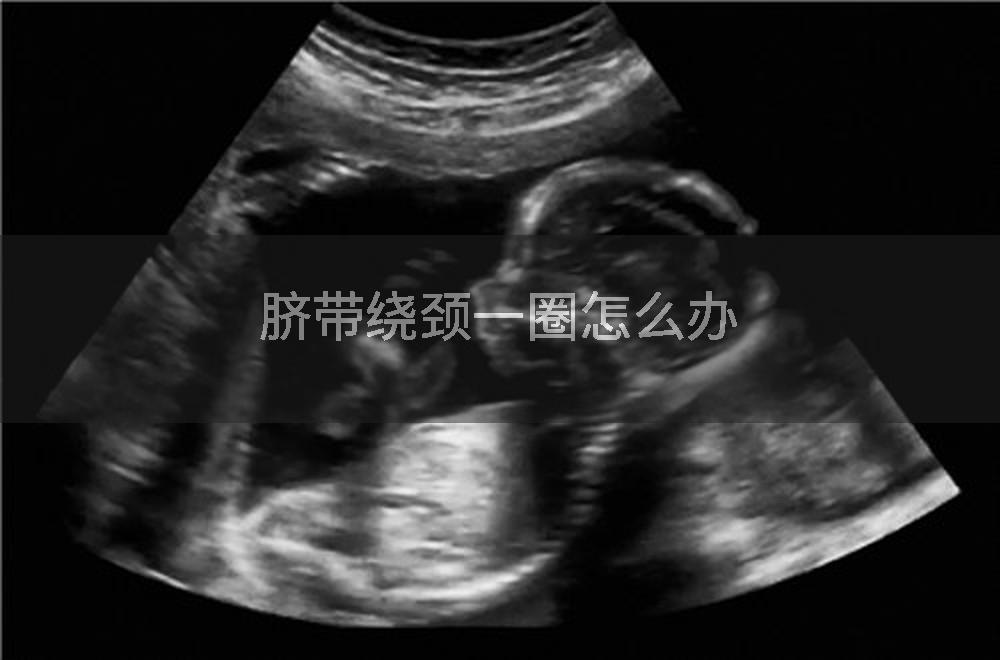

脐带绕颈一圈通常可以通过数胎动、体位调整、吸氧以及必要时终止妊娠等方式处理。孕妇需注意监测胎儿状况,并遵医嘱进行相应干预。

当脐带绕颈导致胎儿宫内窘迫且孕周≥37周时,需立即剖宫产终止妊娠。若未足月但缺氧严重,医生会评估胎儿存活可能性,必要时提前分娩。分娩前需通过超声和胎心监护综合判断绕颈松紧度及胎儿耐受情况。